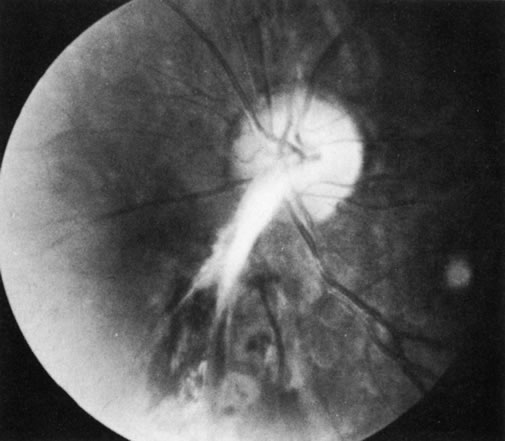

Behçet's disease is a chronic inflammatory disease with widespread clinical manifestations. It affects adults of both sexes, especially in Mediterranean countries and Japan. Classically it consists of a triad of recurrent lesions: iritis, oral ulcers, and genital ulcers (Fig. 6).34 Other common features are vasculitis, skin lesions, optic papillitis (Fig. 7), arthritis, meningomyelitis, and inflammatory bowel disease. Loss of vision is one of its most frequent and serious manifestations. In Japan, the disease is said to be responsible for one-third of all cases of uveitis. Ocular disease occurs in 75% of affected patients, usually in the form of hypopyon, uveitis, occlusive retinal vasculitis, and optic nerve lesions. The cause of Behçet's disease is unknown, but viral, immunologic, and hereditary factors have been suspected.

Fig. 7. Optic papillitis in Behçet's disease. (Courtesy of Dr. G. Mintsioulis.)